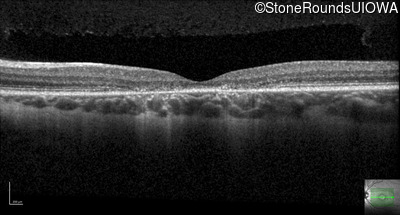

Infrared Fundus Photograph - Right - 20/40 -2

Exemplar

Infrared Fundus Photograph - Left - 20/50 +2